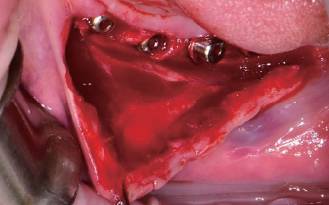

#43, 44, 45 & 46

Implant 식립

Wifi-Mesh 준비

Wifi-Mesh 형태 형성 *

Wifi-Mesh 장착

#33, 34, 35 & 36

골 이식

Wifi-Mesh 위치시킴